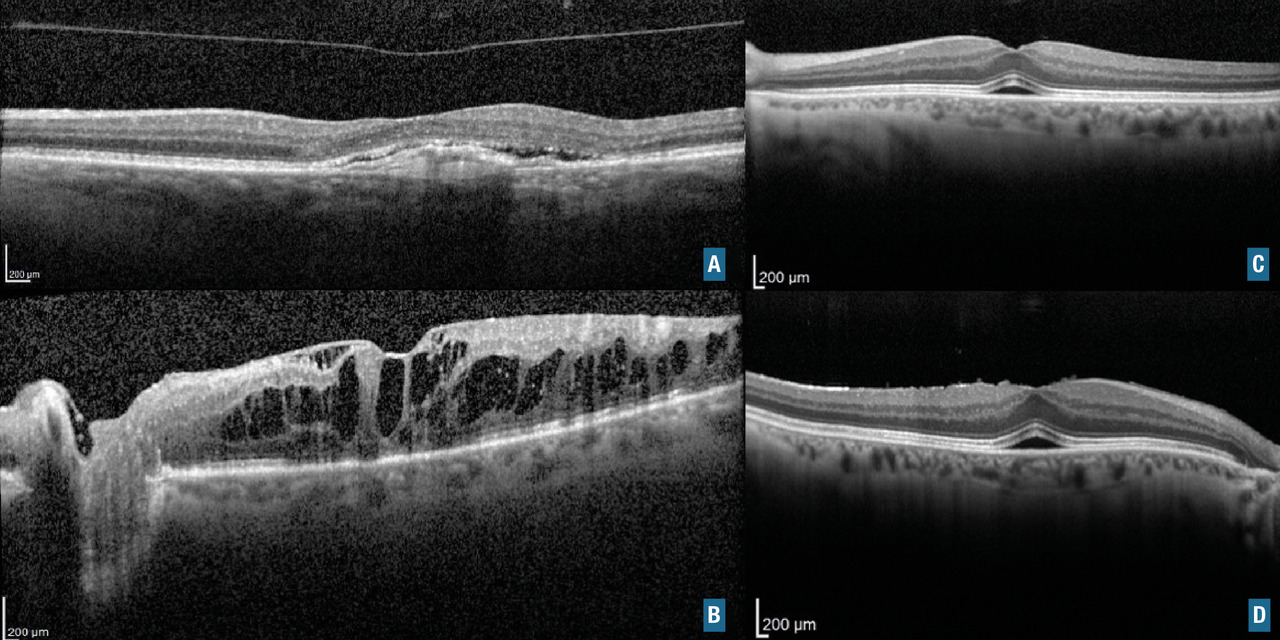

Le diagnostic est le plus souvent posé par l’OCT, avec la présence d’un néovaisseau choroïdien sous rétinien et une activité exsudative avec décollement séreux rétinien. La présence du néovaisseau est initialement confirmée par l’angiographie (fluorescéine ou indocyanine) et l'OCT-angiographie selon le type de néovaisseau (fig. 10A).

L’œdème maculaire est une cause fréquente de baisse d’acuité visuelle progressive (fig. 10B).

Le diagnostic est fait grâce à l’OCT, qui montre un épaississement maculaire avec des logettes intrarétiniennes ou du liquide sous-rétinien. Lorsqu’il est important, une image en « pétales de fleur » peut être visible au fond d’œil.

Membrane épimaculaire et trou maculaire

Ce sont des pathologies de l’interface vitréorétinienne (fig. 11). Les signes fonctionnels constituent le syndrome maculaire : métamorphopsies, baisse d’acuité visuelle et/ou scotome central. Le diagnostic est fait à l’examen du fond d’œil (« reflet cellophane » pour la membrane) et confirmé par l’examen en OCT. La prise en charge thérapeutique est chirurgicale.

Maculopathie aux inhibiteurs de MEK

Les inhibiteurs de MEK agissent sur des voies intracellulaires appelées voie MAPK. Ils sont de plus en plus utilisés en oncologie, notamment dans la prise en charge des mélanomes métastatiques. Les symptômes oculaires surviennent souvent de manière rapidement progressive. L’atteinte rétinienne la plus fréquente se traduit par l’apparition spontanée de plusieurs décollements séreux rétiniens (fig. 10C et D). Ils sont généralement réversibles à l’arrêt du traitement. Parfois, selon la balance bénéfices-risques, on peut décider de poursuivre le traitement sous surveillance.